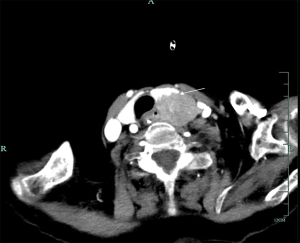

In this study, four patients with functional parathyroid carcinoma underwent preoperative ultrasound (Figure 1) and dual-phase technetium 99m sestamibi (99mTc-MIBI) parathyroid scintigraphy with single-photon emission computed tomography (SPECT)/computed tomography (CT) (Figure 2). The two patients with nonfunctional parathyroid carcinoma had preoperative ultrasound and CT scans (Figure 3). There were 2 cases where the tumors were located in the right neck and 4 cases in the left neck. On ultrasound examination, the smallest tumor measured 2.5 cm in diameter, while the largest was 11.4 cm, with five cases (83.33%) having diameters ≥3 cm (Table 2). Among the four patients with functional parathyroid carcinoma, preoperative PTH levels ranged from 269.8 to 6,012.3 ng/L, with three cases exceeding 10 times the upper limit of normal. All four patients had preoperative serum calcium levels above the upper limit of normal. In contrast, the two patients with nonfunctional parathyroid carcinoma had normal preoperative PTH and calcium levels (Table 2).

The diagnosis of parathyroid carcinoma is extremely challenging, especially preoperatively (18,19). Functional parathyroid carcinoma presents clinically with symptoms identical to those of hyperparathyroidism caused by parathyroid adenomas, making differentiation between the two difficult. Some researchers found that when PTH levels exceed 10 times the upper limit of normal (3) or when serum calcium levels are greater than 3 mmol/L in conjunction with a parathyroid tumor diameter larger than 3 cm, a diagnosis of parathyroid carcinoma should be highly considered (19). In this study, PTH levels exceeded 10 times the upper limit of normal in three cases (50%), and serum calcium levels were greater than 3 mmol/L with tumor diameters larger than 3 cm in two cases (33.3%). However, these characteristics are also present in many parathyroid adenomas and therefore cannot serve as the sole diagnostic criterion. Parathyroid carcinoma may appear as a larger tumor with a diameter often exceeding 3 cm or with unclear margins on ultrasound, CT, or magnetic resonance imaging (Figures 1-3). However, these features can also be observed in parathyroid adenomas. Thus, while imaging studies can help detect and localize parathyroid tumors, diagnosing parathyroid carcinoma based solely on imaging is extremely difficult (20). Most cases of parathyroid carcinoma are diagnosed through postoperative histopathological examination, as was the case with all six patients in this study.